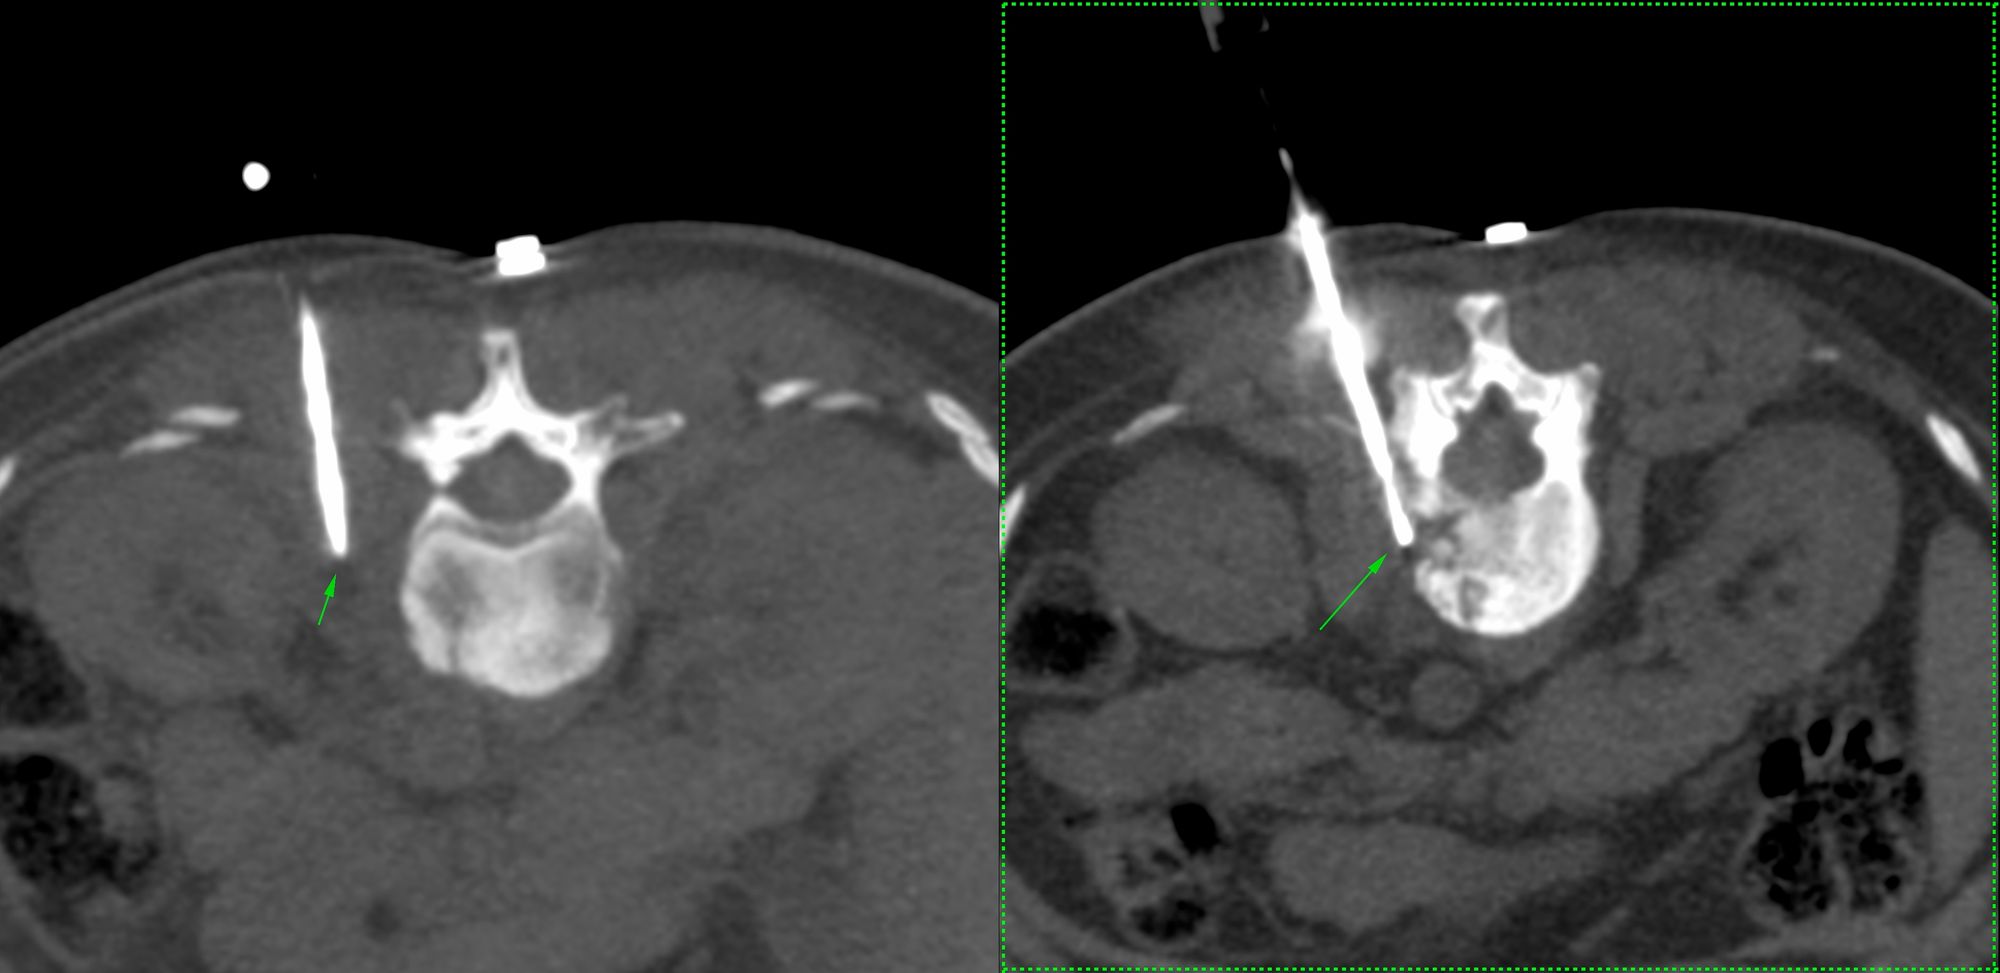

Case 3: Multifocal spine lesions - infectious spondylitis, likely tuberculosis

Bhavin Jankharia - 09 February 2021